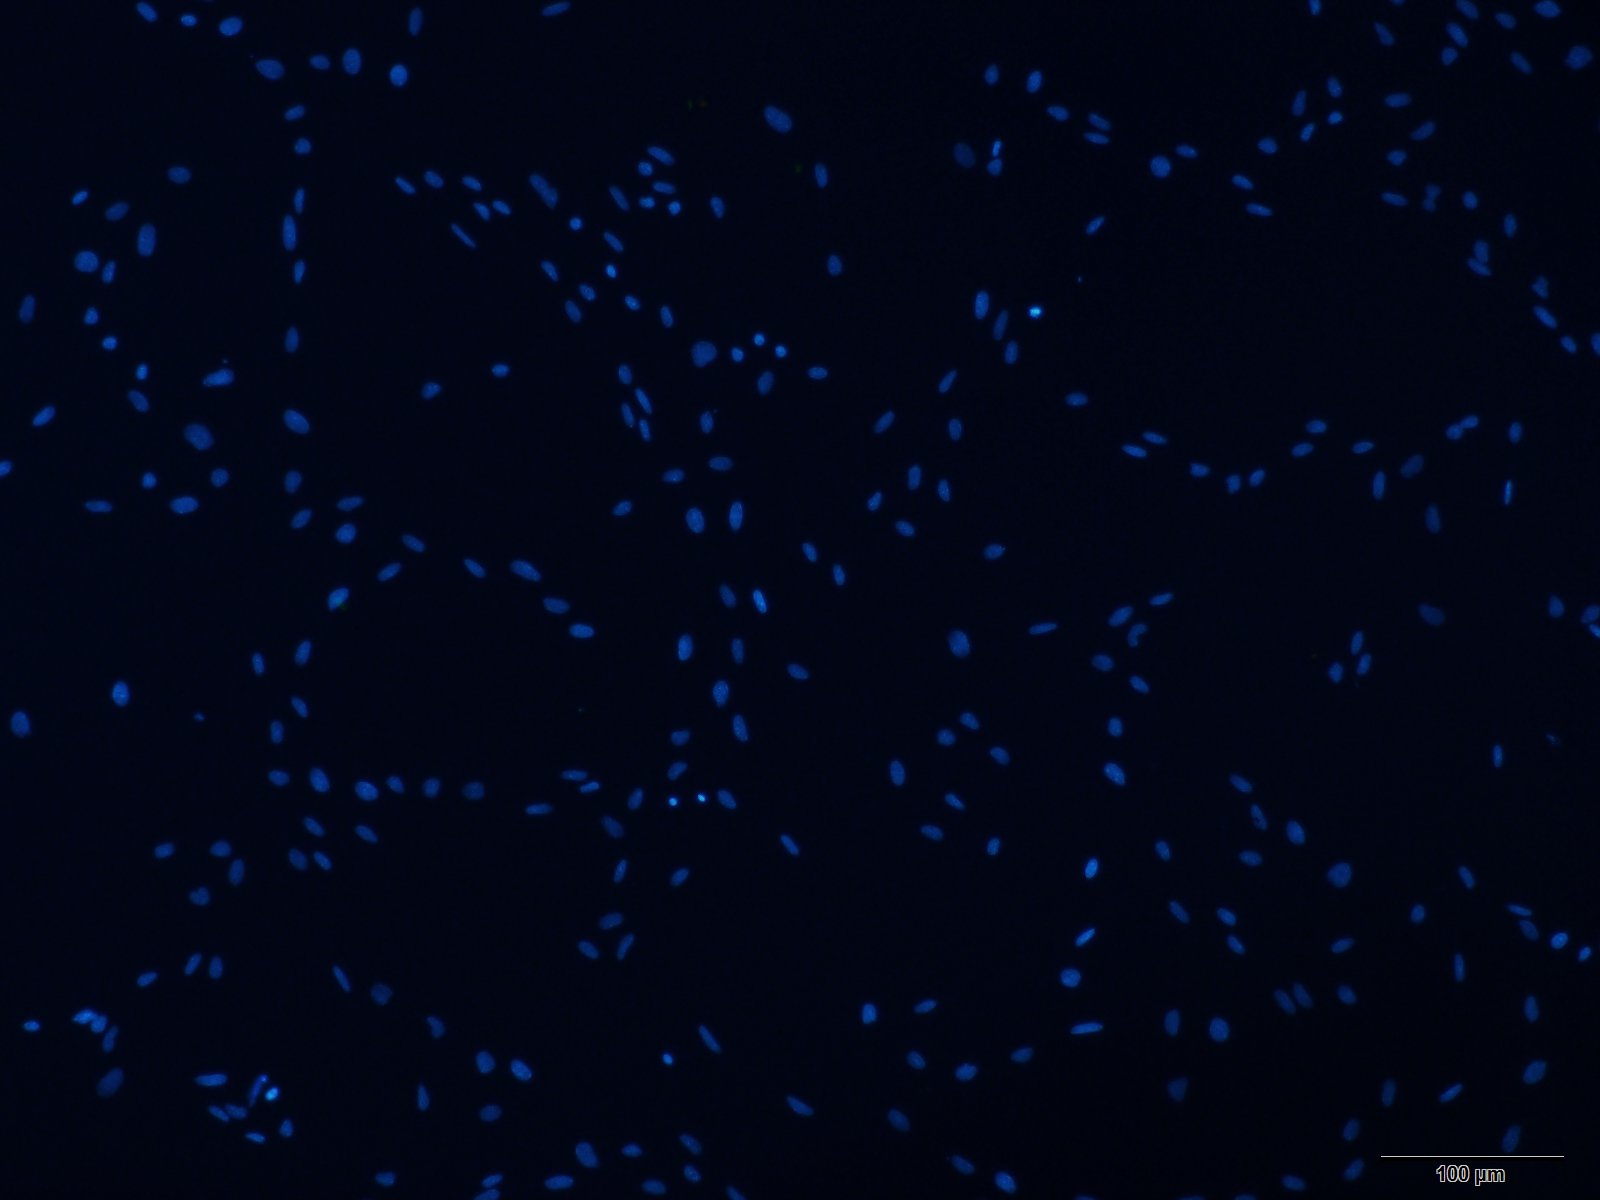

本公司生产的大鼠主动脉平滑肌细胞采用酶解法制备而来,细胞总量约为5×105/T25方瓶,α-SMA、Desmin免疫荧光染色呈阳性,细胞纯度可达90%以上,且不含有HIV-1、 HBV、HCV、支原体、细菌、酵母和真菌等。